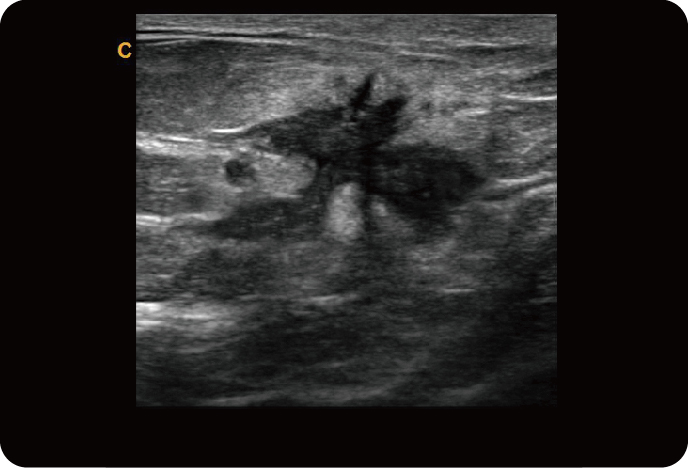

Микро-конвексный